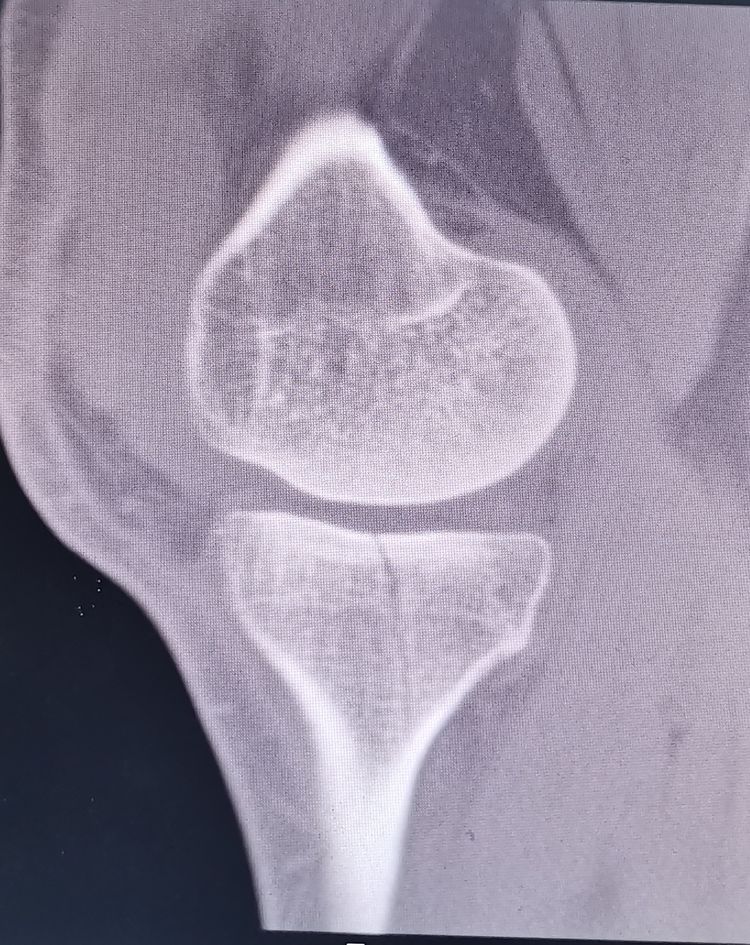

左膝正侧位DR:左膝前交叉韧带胫骨止点撕脱骨折,内侧胫骨平台骨折,均未见明显移位。

左膝CT

初步诊断:1、左膝ACL胫骨止点撕脱骨折 2、左膝胫骨平台骨折(Schatzker Ⅰ型) 3、左膝关节积液